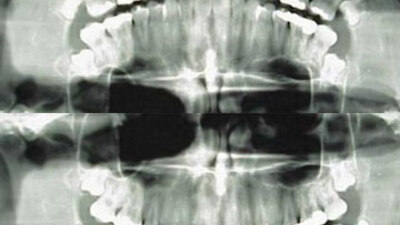

Hem yetişkin hem de çocuklarda diş filminin artık sık olarak kullanılan bir tetkik olduğunu belirten Aktolun, ''Özellikle çocuklara son yıllarda yapılan ortodontik (diş ve çene düzeltme) tedavisinin takibi için her kontrolde, yani neredeyse her ay diş röntgen filmi çekilmektedir. Diş röntgeni, normal küçük boy diş filmi ve panoramik diş filmi olmak üzere iki türdür. Hastalar, küçük diş filmi çekilirken daha az radyasyona maruz kalmaktadır. Ancak, panoramik diş filmi çekilen hastalar çok daha fazla radyasyona maruz kalır'' dedi.

Halbuki diş hekimleri, çocuk hastalara çok sıklıkla diş filmi çektirebilmektedir. Burada diş hekimlerini rahatlatan husus, diş filmlerinde kullanılan radyasyonun miktarının çok düşük olmasıdır. Ancak, düşük de olsa radyasyonun etkileri birikmektedir. Üstelik, son yıllarda daha da sık kullanılan panoramik röntgen tetkikinde, çocuklara ciddi miktarda radyasyon verilmektedir. Bu radyasyondan en çok da tiroid etkilenebilmektedir. İngiltere'de yapılan araştırma, diş röntgenlerinin yaydığı radyasyonun tiroid kanserinde rol oynayabileceğini ortaya çıkarmıştır. Toplam 313 tiroid kanseri hastasının geçmişi incelenerek yapılan ve aynı zamanda aynı sayıda aynı yaş ve cinsiyette karşılaştırmalı bir hasta grubu da kullanan bu meta analiz çalışmasında tiroid kanseri riskinin, geçmiş yıllarda diş röntgeni çektirmiş hastalarda ortalama 2 kat arttığı belirlendi.''